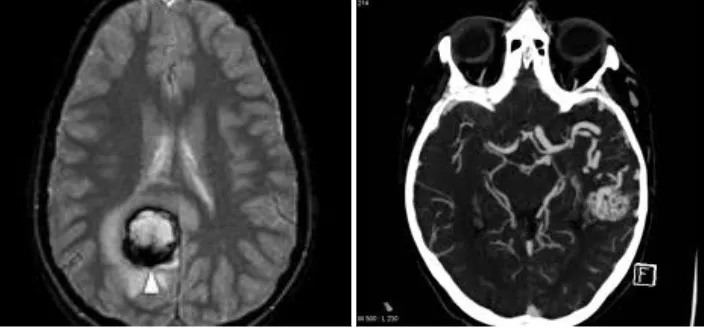

Un aneurisma cerebral es una dilatación de la luz arterial, es decir, un ensanchamiento anormal en la pared de una arteria del cerebro. En el ámbito cerebral, los aneurismas adoptan fundamentalmente dos formas:

- Saculares: son los más frecuentes (más del 90% de los aneurismas cerebrales). Se desarrollan en forma de saco que va creciendo progresivamente a partir de un punto débil de la pared arterial.

- Crecimiento con trombosis y embolias: cuando el aneurisma crece sin romperse, la circulación sanguínea en su interior se enlentece, se forman trombos que pueden desprenderse y generar embolias cerebrales.

- Aneurisma gigante como masa expansiva: en casos excepcionales, el aneurisma alcanza un tamaño tan grande que se comporta como un tumor, comprimiendo las estructuras cerebrales vecinas y produciendo daño por efecto de masa.

Una vez confirmada la hemorragia, es necesario identificar el aneurisma responsable. Para ello se emplean la angio-TAC (TAC con contraste vascular) y el estudio angiográfico cerebral (arteriografía), que no solo permiten localizar y caracterizar el aneurisma antes de la intervención, sino que también sirven para comprobar que el aneurisma se ha cerrado correctamente tras el tratamiento.